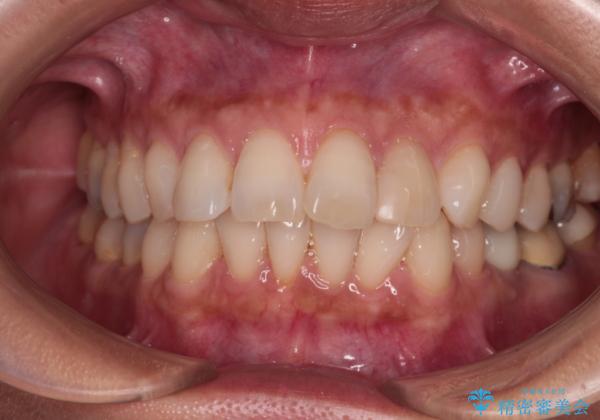

むし歯と前歯のデコボコを治したい インビザラインを使用した総合歯科治療

- 目立つ銀歯やむし歯、前歯のデコボコを気にして来院された患者様です。

デコボコはある程度改善できれば良いとのことでしたので、インビザラインの廉価版を用いて矯正治療を行うこととしました。

飛行機での通院であり、更にはご家族がの都合で海外に滞在されることも多いため、中等度の歯列不正に対応可能なインビザライン・モデレートパッケージを使用することとしました。

むし歯治療は、症状のある歯を矯正治療前に処置し、概ね歯列が整ったところで残りのは全て処置し、最後にインビザラインで歯列を仕上げることで、無駄なく治療を進めて行くこととしました。

しっかりと装着時間を守ってくださり、来院のタイミングに合わせてインビザラインの装着期間を調整するなど、協力いただいたおかけで、1年半の期間で全てを終えることができました。